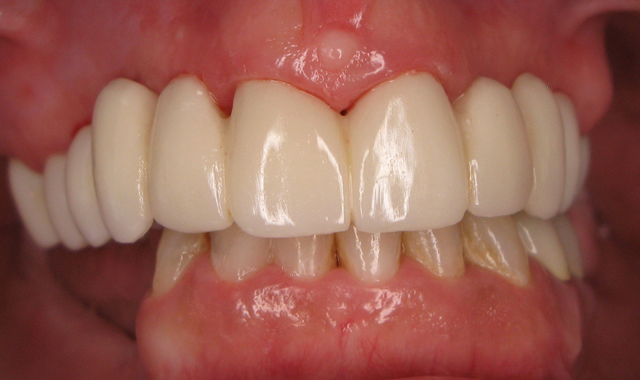

Here is the finished case before sending it back to the dentist (Figs. 23-25) and here is the final seated case (Figs. 26-28).

Fig. 25                                                                   Fig. 26

As you can see from the picture, the patient was extremely happy with her permanent smile and so was the doctor.